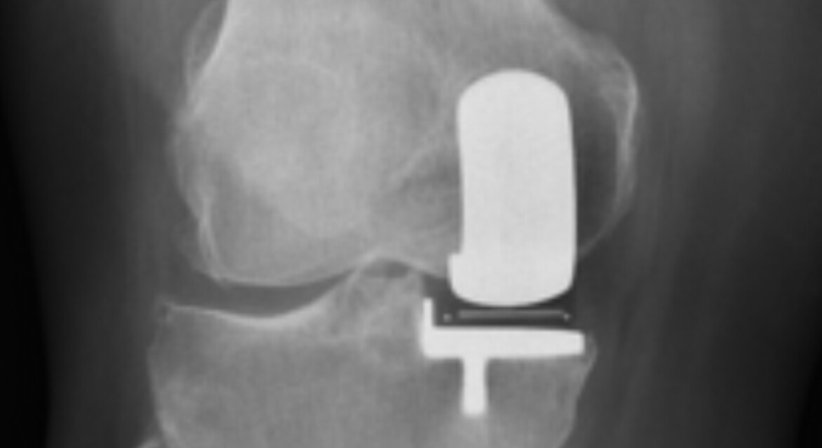

Knieendoprothese / KTEP bzw. medialer Halbschlitten

bei Arthrose des Kniegelenks / Gonarthrose und Ausschöpfen der nicht operativen Therapie

bei isolierter Medialarthrose kann auch ein Teilgelenksersatz erfolgen